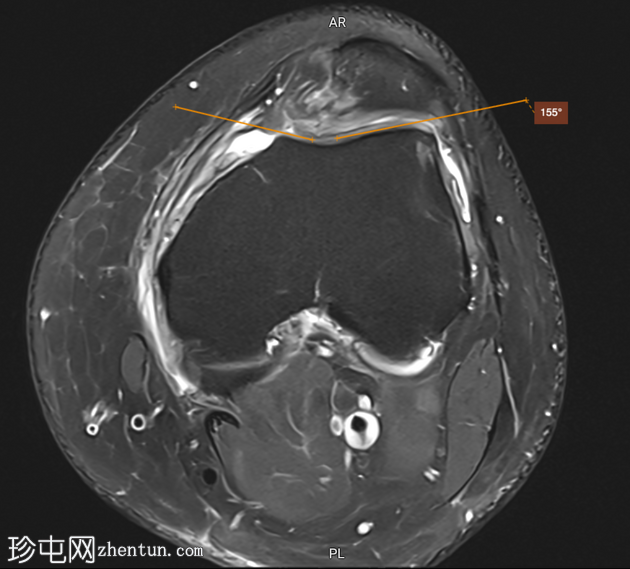

轴位PD序列

脂肪抑制序列

角度

滑车深度 < 3 mm

滑车沟角度 > 150°

滑车外侧倾斜度 < 11°

影像学表现符合滑车发育不良